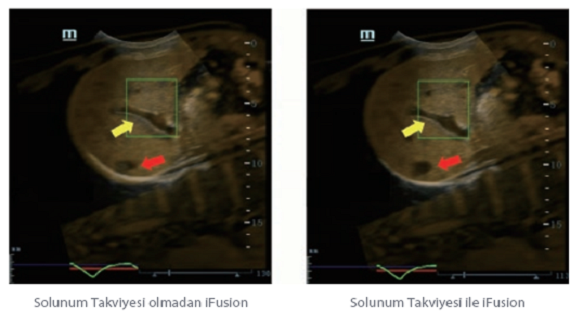

Mindray, ?irketin kuruldu?u gĂŒnden bu yana sĂŒrekli olarak tan?sal do?rulu?u iyile?tirmeye ?al??maktad?r. Devrim niteli?indeki ZONE Sonography? Teknolojisi ile desteklenen Resona 7ânin yeni ZST+ platformu, b?lge g?rĂŒntĂŒsĂŒ alma ve kanal veri i?leme ?zellikleri ile ultrason g?rĂŒntĂŒsĂŒ kalitesini daha ĂŒst bir dĂŒzeye ??kar?yor.

Resona 7, ĂŒstĂŒn dĂŒzeyde g?rĂŒntĂŒ kalitesine ek olarak, vaskĂŒler hemodinamik de?erlendirmesi i?in devrim niteli?indeki V Ak??? ile fetĂŒs CNS tan?lamas? i?in 3 boyutlu veri kĂŒmesinden dĂŒzlem g?rĂŒntĂŒsĂŒ alma konusunda en iyi birime sahip oldu?undan, klinik ara?t?rma yeterliklerini de art?rmaktad?r. En sezgisel, harekete dayal? ?oklu dokunmatik i?letim ile tĂŒm temel klinik ?zellikleri bir araya getiren Resona 7, ultrason yenili?i konusunda ger?ek anlamda yeni dalgalara ?ncĂŒlĂŒk ediyor.